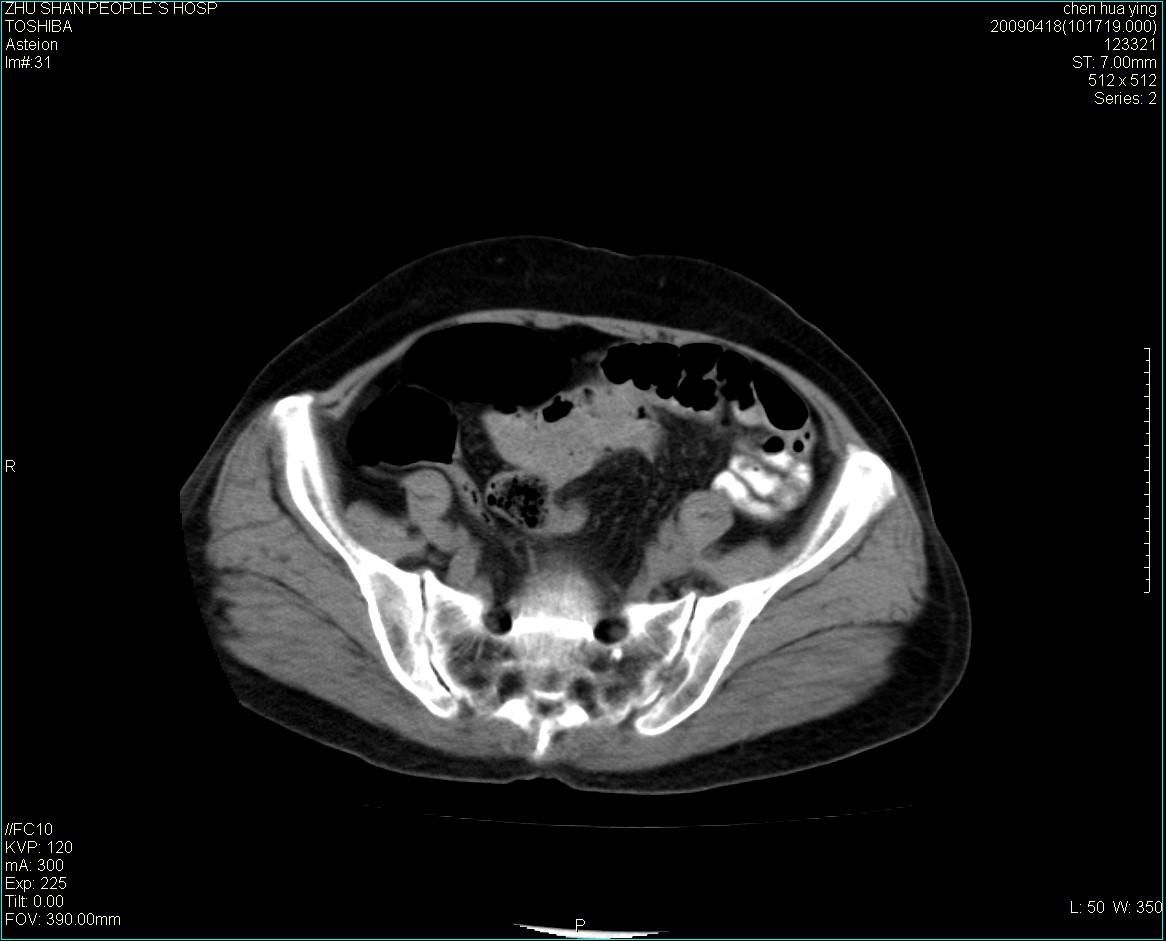

女性病人 65岁 腹部包块半年余结肠造影未见异常.

病灶略呈圆形有分叶状,上部层面呈实性,右侧见圆形低密度区,灶内见团块状钙化,病灶下方与肠管分境不清,考虑间质瘤可能性大,建议肠道准备后增强